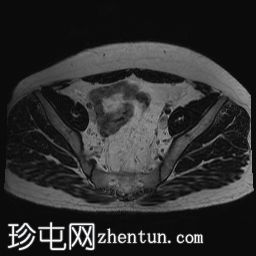

轴位

T2加权像

2.jpg

双侧睾丸均未在阴囊内显露,而是位于盆腔腹股沟管上部。

-左侧睾丸大小为2.6 cm x 1.6 cm x 2 cm。

-右侧睾丸大小为2.6 cm x 1.2 cm x 1.1 cm。

双侧隐睾(睾丸未降)位于盆腔腹股沟管上部。